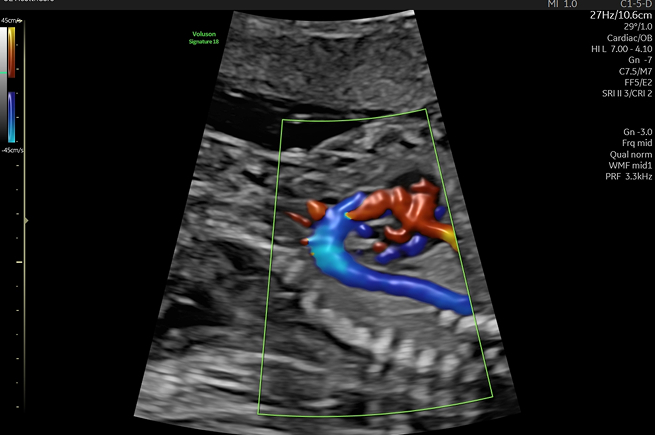

정밀 초음파

태아의 장기가 완성되는 시기에 머리부터 발끝까지 형태적 이상이 없는지 확인합니다.

뇌, 심장, 척추, 복부 장기, 손발가락 등을 세밀하게 관찰하여 태아의 건강 상태를

정확히 진단하는 매우 중요한 검사입니다.